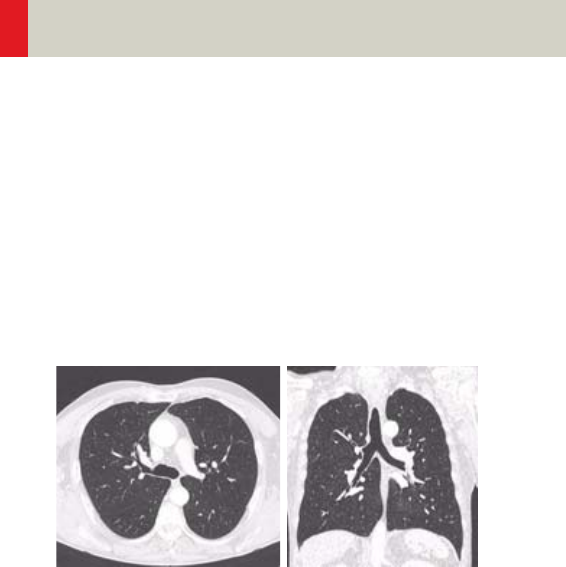

- Embolism/

Embolism06s 394

- HeadTraumaSeq 432

- Additional Important Information 434